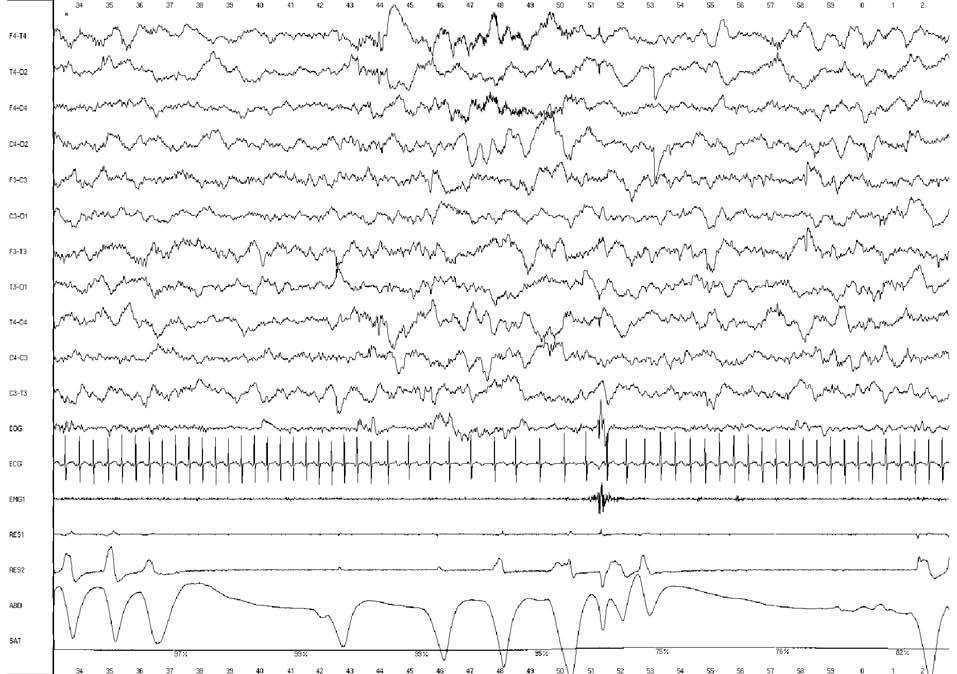

La VPSG consistió en el registro simultáneo de 11 canales de EEG con derivaciones bipolares, del EOG (1-2 canales), del ECG (1 canal), del EMG submentoniano (1 canal), del flujo aéreo nasobucal (2 canales) y del esfuerzo respiratorio torácico y abdominal (2 canales). El flujo nasobucal se ha registrado mediante un sensor de presión de flujo (cánulas nasales), que tiene un gran interés diagnóstico y ha desplazado el registro mediante termistancias. Las termistancias detectan aceptablemente los diferentes tipos de apneas, pero en cambio no son fiables en el registro de las hipopneas y no detectan las limitaciones inspiratorias de flujo (LIFA) y el ronquido. Las cánulas, al igual que las gafas nasales, utilizadas en oxigenoterapia, se insertan en los orificios nasales. Con las cánulas registramos perfectamente las hipopneas, ya sean centrales u obstructivas, y las LIFA. La curva de saturación de oxihemoglobina, obtenida a partir de un pulsioxímetro, se deriva a un canal del polígrafo digital y se obtiene el valor de la SaO2 por segundo (fig. 1). No se ha registrado la PCO2 transcutánea. La duración de la monitorización fue de 2 h, se efectuó en posición de decúbito supino e incluyó dos ciclos de sueño (sueño activo-sueño tranquilo). Iniciamos el registro durante la toma alimentaria para observar si se efectuaba con normalidad o si por el contrario se producía atragantamiento, regurgitación, succión defectuosa, bradicardia y desaturaciones de oxígeno.

Figura 1.Registro polisomnográfico (30 s) de un prematuro nacido a las 34 semanas de edad gestacional, efectuado a las 3 semanas de vida, EC: 37 semanas, durante una fase de sueño tranquilo. El EEG muestra un patrón de actividad discontinua, ausencia de movimientos oculares rápidos, EMG submentoniano con escasa actividad, respiración regular y SaO2 del 98 %. El registro es normal. Montaje: EEG (11 canales, derivaciones bipolares); oculogramas derecho e izquierdo (EOG1 y EOG2); ronquido (RES1); flujo nasal registrado con cánulas (RES2); esfuerzo abdominal (RES3) y SaO2. Sensibilidad = 10 mV/mm. Filtro de red = 50 Hz.